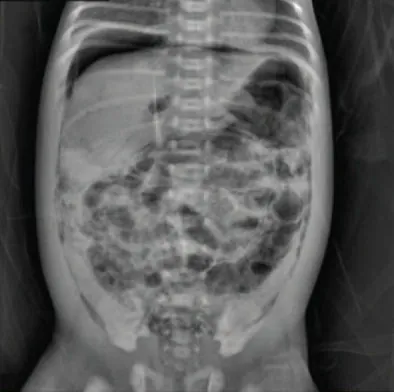

NEC is clinically diagnosed from the symptoms presented by the infantโ€”abdominal distention, bilious vomiting, and rectal bleeding with bloody stoolโ€”along with an x-ray of the abdomen showing pneumatosis intestinalis, intramural gas in the intestines (Figure 25.17). The only definitive diagnosis is made with a surgical sample or a postmortem assessment with tissue that shows histologic findings of intestinal inflammation, infarction, and necrosis.

An x-ray image of an infant shows gas patterns within the intestinal wall characterized by dark, circular areas against the denser background of the abdomen. The patterns are irregularly distributed throughout the intestine.

Figure 25.17 x-ray of an Infant with NEC This photo shows an abdominal film with pneumatosis intestinalis, a radiologic sign seen in patients with necrotizing enterocolitis (NEC). The abdominal x-ray shows the intramural air bubbles that occur in the bowel wall from gas produced by bacteria in the intestinal wall lining. Note the bubbly lucencies filling the abdominal cavity. (credit: โ€œPneumoperitoneum and Pneumatosis Intestinalisโ€ by Sheng Q, Lv Z, Xu W, Liu J, Wu Y, Shi J, Xi Z. /Wolters Kluwer Health, CC BY 4.0)